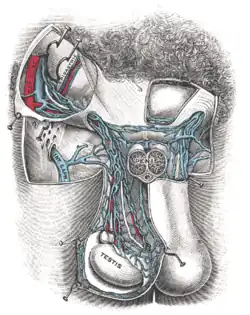

Eine Varikozele, Varicocele testis (von lateinisch varix „Krampfader“, und griechisch kele „Bruch“) oder ein Krampfaderbruch ist eine Krampfaderbildung im Bereich des von den Hodenvenen gebildeten Plexus pampiniformis, eines Venengeflechts im Samenstrang. In 75 bis 90 Prozent[1] der Fälle tritt die Varikozele linksseitig auf. In der Regel bedarf die Varikozele keiner Therapie. Unbehandelte Varikozelen sind eine häufige Ursache für männliche Unfruchtbarkeit.

Die Ursache für linksseitige Varikozelen dürfte vor allem die ungünstige Einstrombahn der linken Vena testicularis (Hodenvene) in die linke Vena renalis (Nierenvene) sein, welche in einem Winkel von etwa 90 Grad auf die V. renalis eintrifft. Daraus folgt ein höherer Venendruck auf der linken Seite, welches das Entstehen der Varikozele begünstigt. In seltenen Fällen treten auch symptomatische Varikozelen, beispielsweise durch einen Nierentumor bedingt, auf.